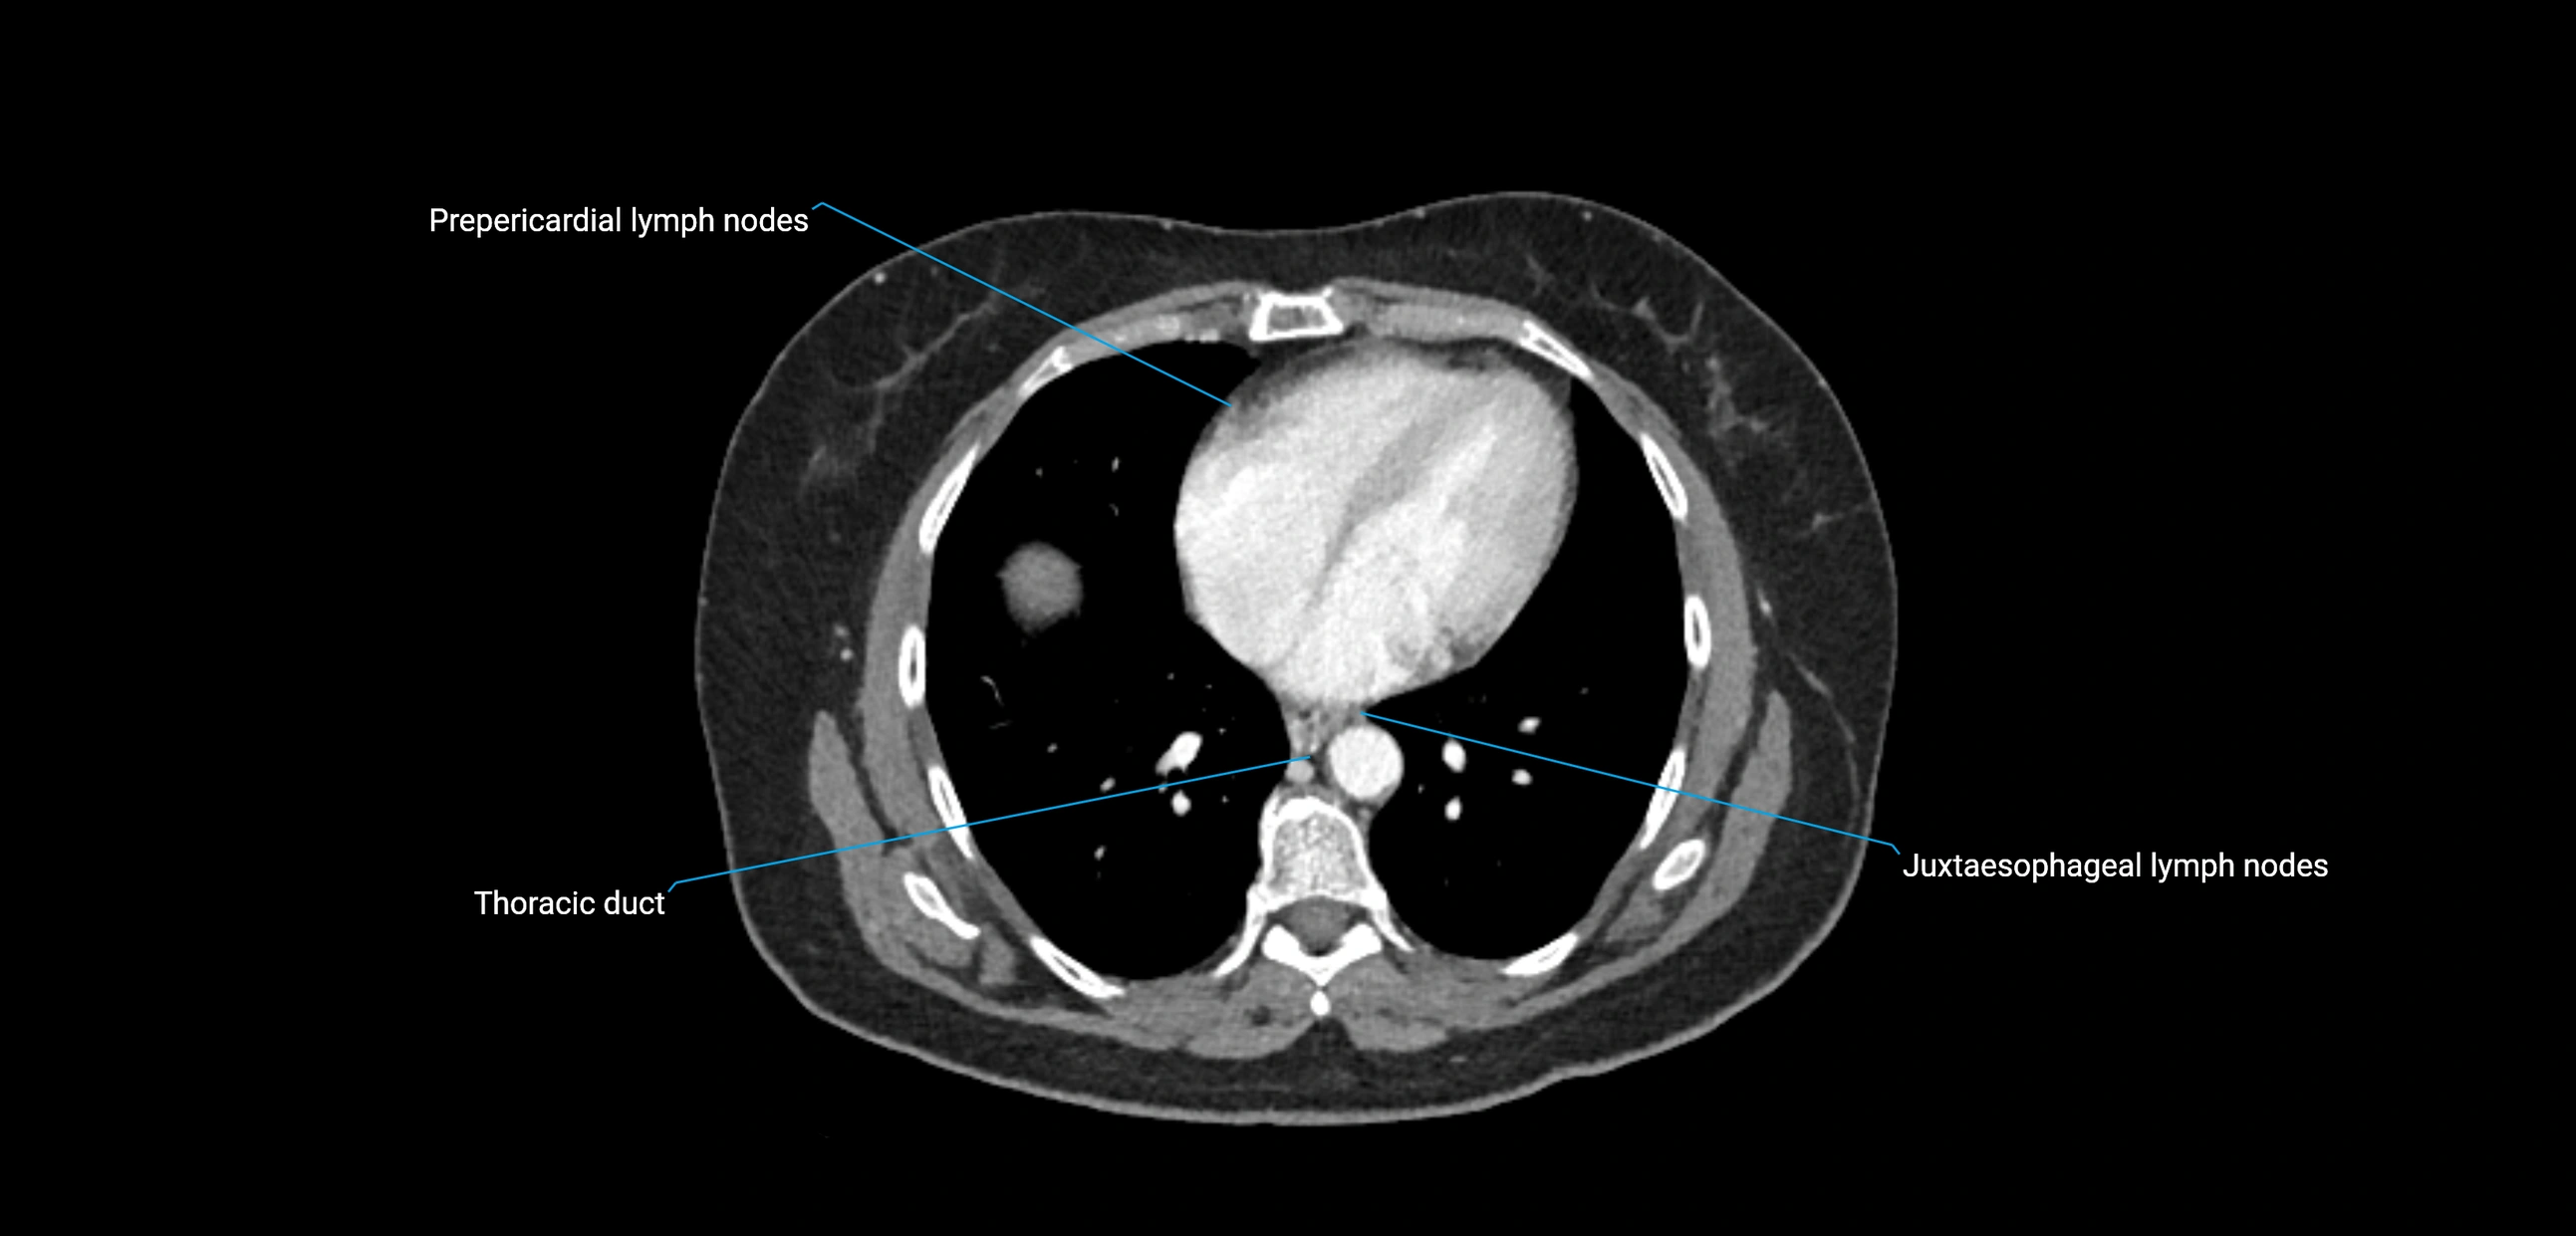

CT Appearance

CT Pre-Contrast:

• Nodes appear as soft-tissue density nodules adjacent to the aorta and IVC

• Calcification may be seen in chronic infections (e.g., tuberculosis)

CT Post-Contrast:

• Normal nodes enhance homogeneously

• Malignant nodes may show heterogeneous enhancement, central necrosis, or conglomerate formation

• Size >1 cm short axis is suspicious, though morphology and distribution are equally important